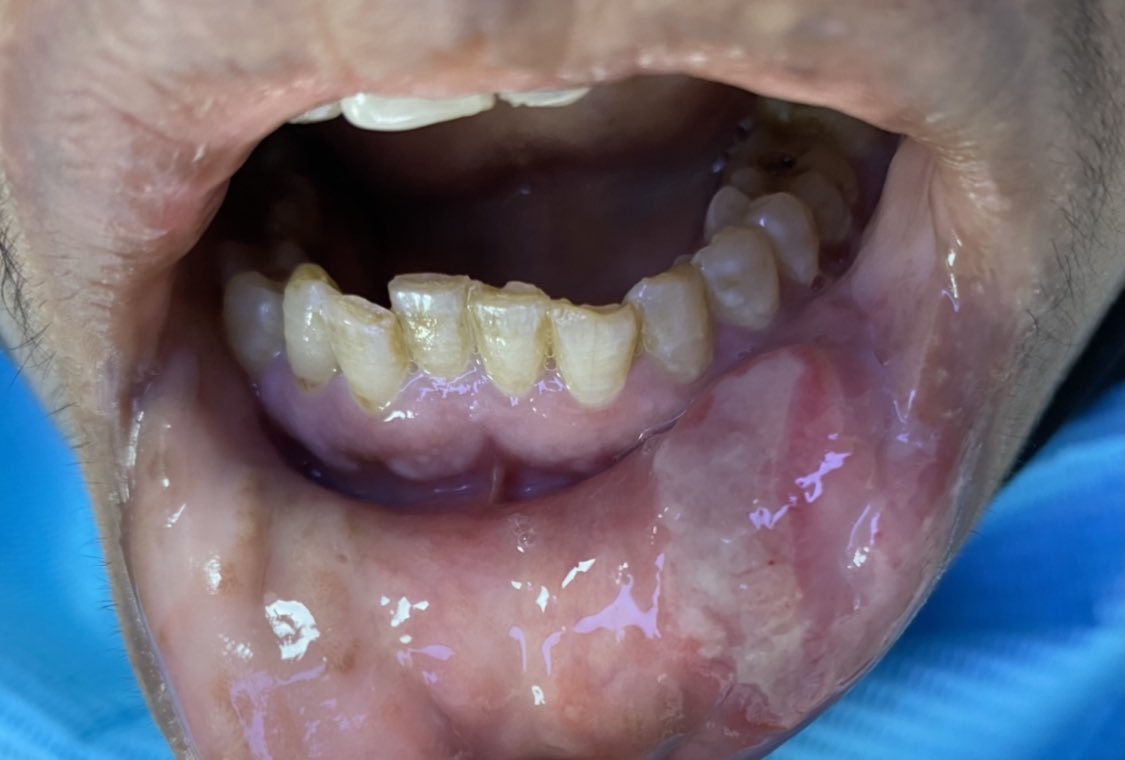

▪️الشكل الثاني: القرحة القلاعية الكبرى (الصورة المرفقة)

▪️الشكل: دائري إلى بيضاوي لا يتجاوز قطرها ١٠ ملم ويمكن أن تصيب أي مكان في الغشاء المخاطي للفم باستثناء اللثة والحنك الأمامي (ميزة مهمة للتشخيص)

▪️اللون: عادة غشاء أبيض قريب للصفرة في المنتصف مع هالة حمراء في الاطراف